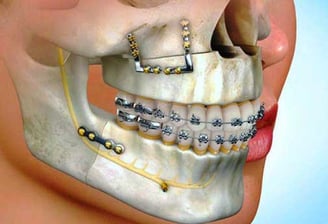

Surgical Orthodontics

For complex cases involving jaw discrepancies, surgical orthodontics may be necessary. Our team collaborates with oral surgeons to correct these issues, enhancing both function and facial aesthetics.